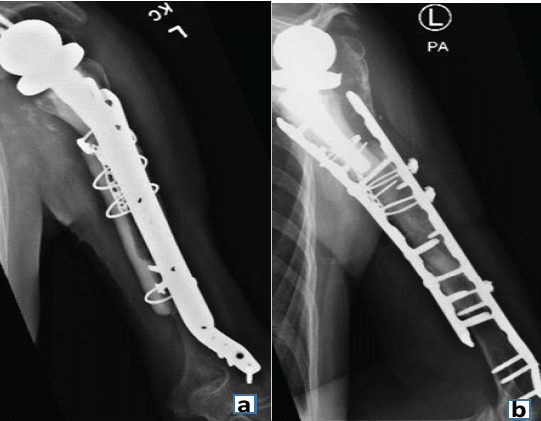

During the next 2 years, she had little pain but continued loss of ROM. At 26 months after the last operation, she developed a sense of instability, with the feeling that something was moving in the arm. Conventional radiographs showed that the custom tumor prosthesis had fallen into varus and was eroding through the humerus (Fig. 6).

Figure 6: Anteroposterior radiograph showing reduction of the fracture, secured in place with a fibular allograft strut and long plate. The humeral component gradually loosened and migrated into varus, as seen here.

Laboratory tests and aspiration showed no signs of infection. Magnetic resonance imaging of the shoulder showed a moderate-grade partial tear in the supraspinatus tendon (3–4 mm) but no evidence of tendon retraction. Because her pain became intolerable, she underwent another revision, and histological testing did not find any signs of infection. At the time of surgery, the humeral component was found to be completely loose. The humeral stem was removed manually along with the cement distally, with no difficulty. Specimens obtained at the time of surgery did not demonstrate any signs of infection on histological analysis. An allograft-prosthetic composite (APC) was then used to reconstruct the proximal humerus. The APC was constructed with a cemented short-stem humeral component (Zimmer Biomet) in the proximal humeral allograft. The APC was fixed internally to the existing humerus and previously placed allograft using 2 plates (Fig. 7).

Figure 7: Anteroposterior (a) and lateral (b) radiographs showing finished reconstruction using allograft and plate.